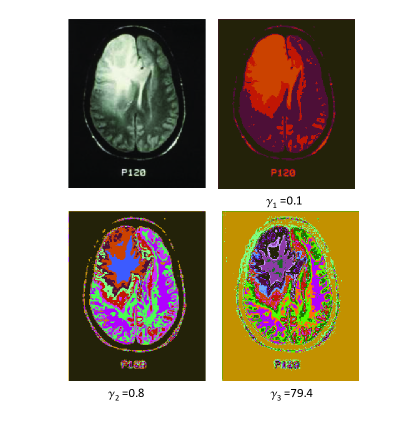

(b) The unweighted result of the brain images with different γ𝛾\gamma, which correspond to γ1=0.1subscript𝛾10.1\gamma_{1}=0.1, γ2=0.8subscript𝛾20.8\gamma_{2}=0.8, γ3=79.4subscript𝛾379.4\gamma_{3}=79.4.

Figure 5: [Color Online.] The plot of the normalized mutual information INsubscript𝐼𝑁I_{N}, variation of information V𝑉V and the number of communities q𝑞q as a function of γ𝛾\gamma for the brain image. This image is reproduced with permission from the Iowa Neuroradiology Library. The axis for γ𝛾\gamma is on a logarithmic scale. There are three prominent peaks in the V𝑉V curve. We apply our community detection algorithm to the grey-scale brain image at these three values of γ𝛾\gammas. The corresponding results are shown in panel (b). Note that the results show three-level hierarchy as γ𝛾\gamma varies.

We start the review of the results of our methods by analyzing an unweighted graph (Eq. (1)) for the grey-scale brain image as shown in Fig. 5. We will assign edges between pixels only if the intensity difference is less than the threshold V¯=16¯𝑉16\bar{V}=16 as denoted in panel (a) of Fig. 5. The algorithm uses Eq. (1) to solve for a range of resolution parameters γ𝛾\gamma in the interval [γ0,γf]subscript𝛾0subscript𝛾𝑓[\gamma_{0},\gamma_{f}]. In the particular case in Fig. 5, γ0=103subscript𝛾0superscript103\gamma_{0}=10^{-3} and γf=100subscript𝛾𝑓100\gamma_{f}=100. There are two more input parameters that are needed in our algorithm: the number of independent replicas r𝑟r that will be solved at each tested resolution and the number of trials per replica t𝑡t. We use r=10𝑟10r=10 and t=4𝑡4t=4 in Fig. 5 respectively.

The plots of INsubscript𝐼𝑁I_{N}, V𝑉V and q𝑞q as a function of γ𝛾\gamma in Fig. 5 exhibit non-trivial behaviors. Extrema in INsubscript𝐼𝑁I_{N} and V𝑉V correspond to jumps in the number of communities q𝑞q. In the low γ𝛾\gamma region, i.e., γ<0.1𝛾0.1\gamma<0.1, the number of communities is stable. However, when γ>0.1𝛾0.1\gamma>0.1, the number of communities q𝑞q sharply increase. This indicates that the structure changes rapidly as the resolution γ𝛾\gamma varies. There are three prominent peaks in the V𝑉V (variation of information) curve. We show the corresponding images at these resolutions, that is in panel(b) in Fig. 5. These corresponding segmented images show more and more sophisticated structures. The lower right image at a resolution of γ=79.4𝛾79.4\gamma=79.4 shows the information in detail. Different colors in the image correspond to different clusters. There are, at least, five contours surrounding the tumor, that denote the degree by which the tissue was pushed by the tumor. The lower left image at the resolution γ=0.8𝛾0.8\gamma=0.8 is less detailed than the one on the right. Nevertheless, it retains the details surrounding the tumor. If we further decrease γ𝛾\gamma, the upper right image at the resolution γ=0.1𝛾0.1\gamma=0.1 will not keep the details of the tumor boundary, only the rough location of the tumor. Thus, neither too large nor too small resolutions are appropriate for tumor detection in this image. The resolution around γ=0.8𝛾0.8\gamma=0.8 is the most suitable in this case. This is in accord with our general found maxim in Section IX concerning a value of γ=1𝛾1\gamma=1. We re-iterate that, in general, the optimal value of γ𝛾\gamma is found by Eq.(21) (an example of which is manifest in the information theory plateaus discussed in Section VII.2). In Section XI.7, we will discuss, in depth, how the optimal values of γ𝛾\gamma may be determined in (weighted) example systems.